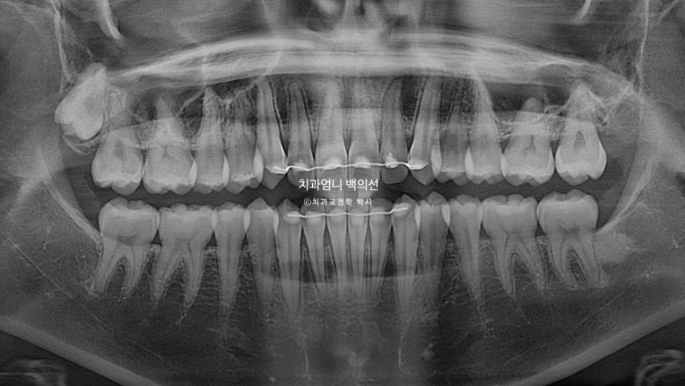

치근흡수는 없으며 치근평행도는 좋습니다.